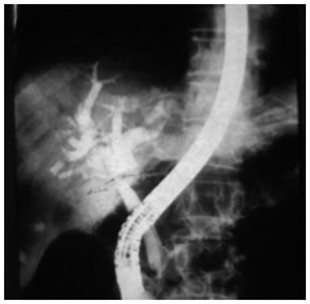

PTBD gram showing type II biliary stricture